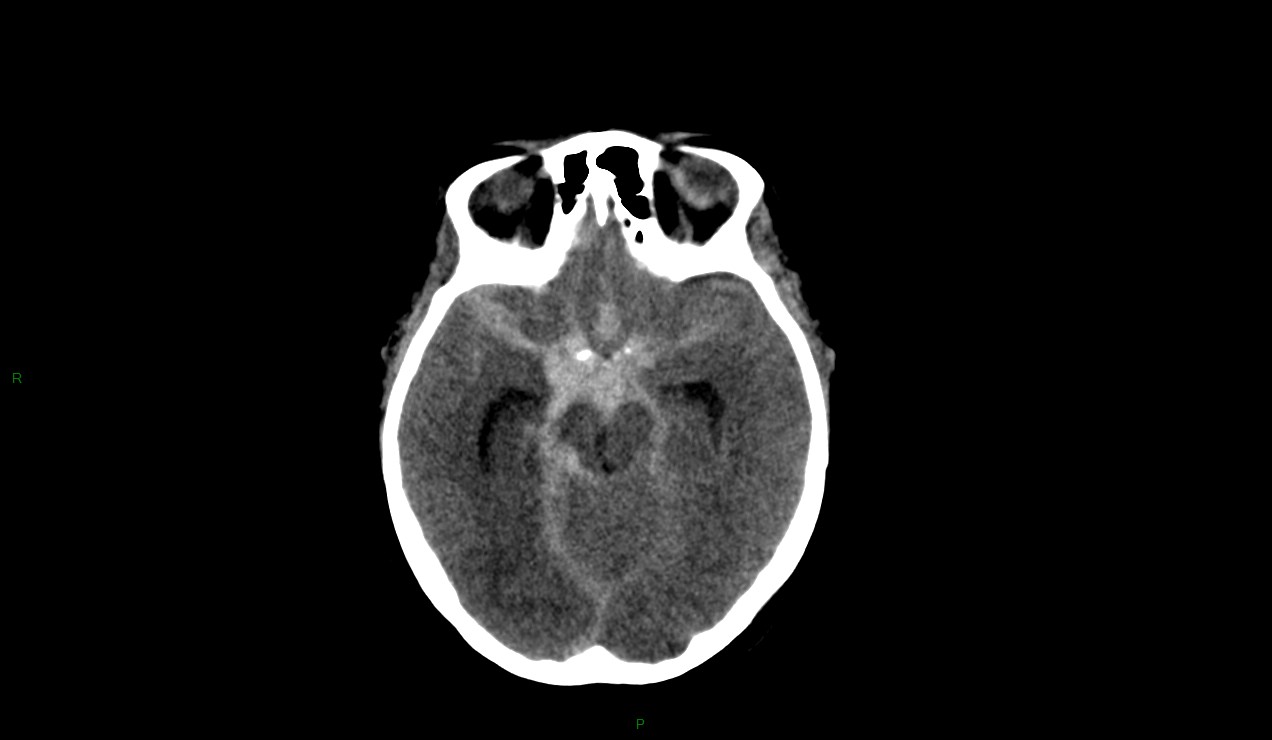

Hémorragie méningée grade 3